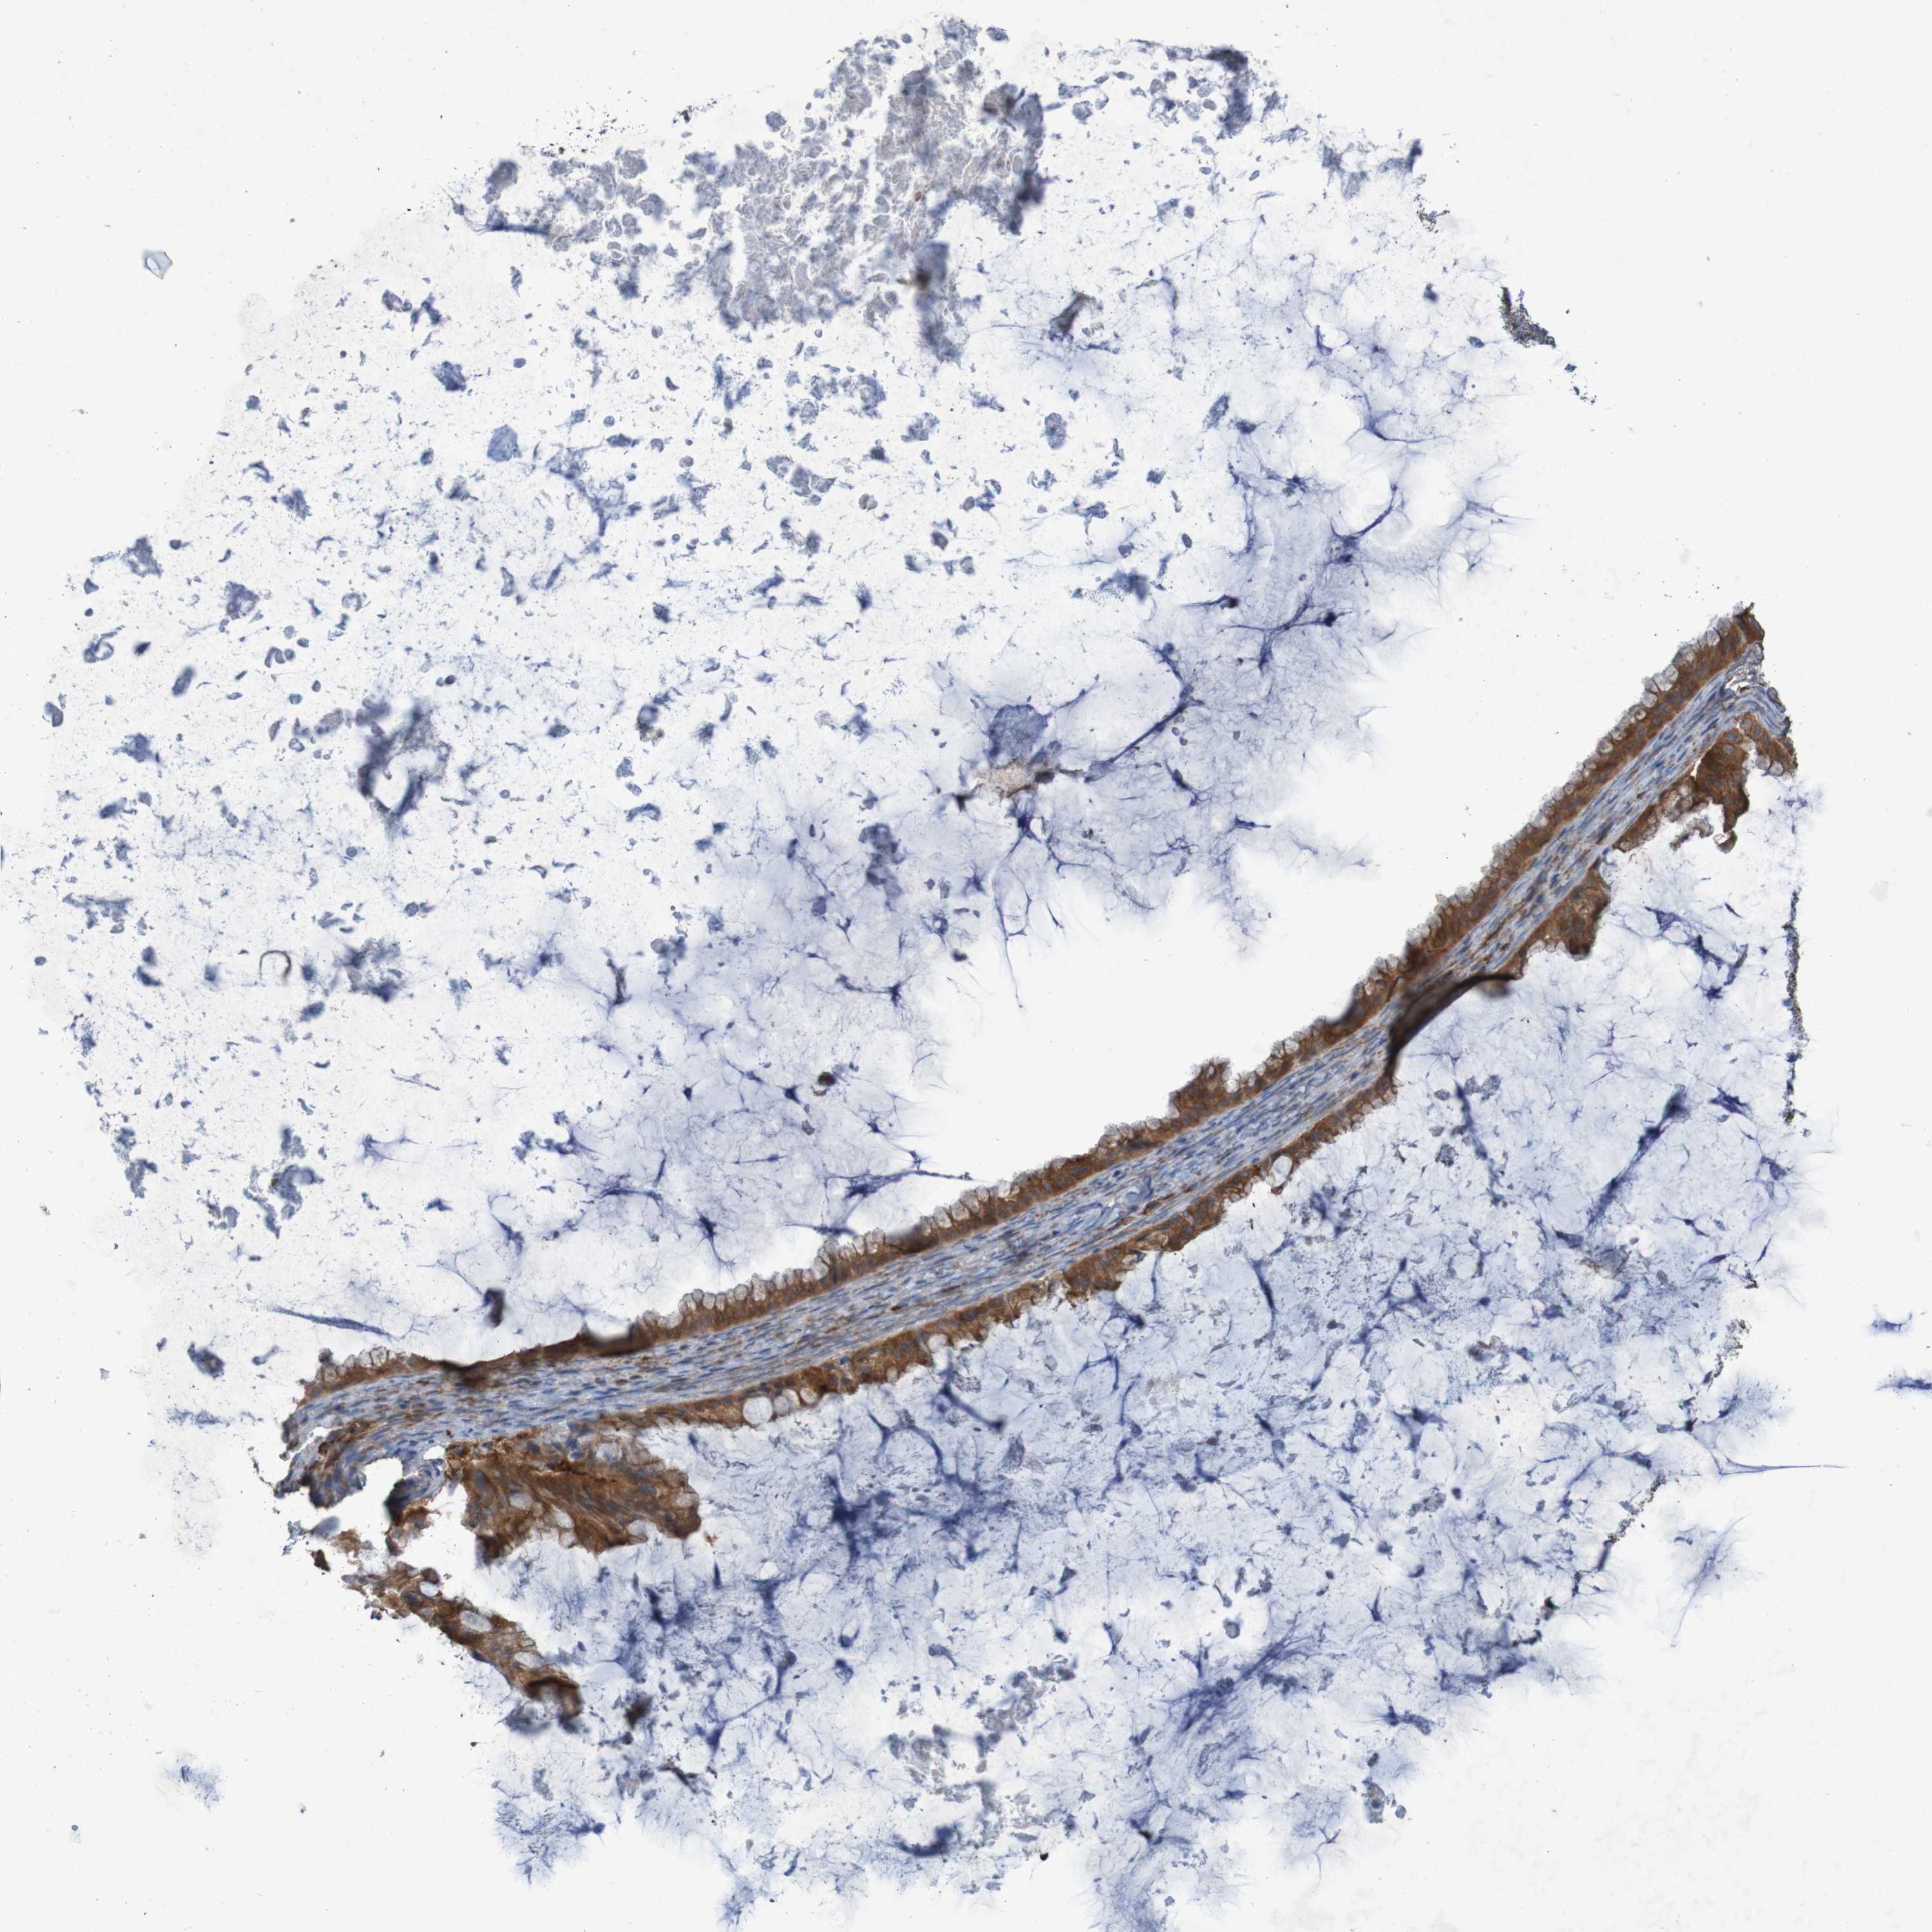

OVARIAN CANCER - Protein expressioni

A mouse-over function shows sample information and annotation data. Click on an image to view it in a full screen mode. Samples can be filtered based on level of antibody staining by selecting one or several of the following categories: high, medium, low and not detected. The assay and annotation is described here.

Note that samples used for immunohistochemistry by the Human Protein Atlas do not correspond to samples in the TCGA dataset.

Antibody stainingi

Antibody staining in the annotated cell types in the current human tissue is reported as not detected, low, medium, or high, based on conventional immunohistochemistry profiling in selected tissues. This score is based on the combination of the staining intensity and fraction of stained cells.

Each image is clickable and will lead to virtual microscopy that enables deeper exploration of all samples and also displays staining intensity scores, fraction scores and subcellular localization as well as patient and tissue information for each sample.

Antibody HPA010980

Antibody HPA011408

Staining

High

Medium

Low

Not detected

Intensity

Strong

Moderate

Weak

Negative

Quantity

>75%

75%-25%

<25%

None

Location

Nuclear

Cytoplasmic/membranous

Cytoplasmic/membranous,nuclear

Cystadenocarcinoma, serous, NOS

Carcinoma, endometroid

Cystadenocarcinoma, mucinous, NOS

Carcinoma, NOS